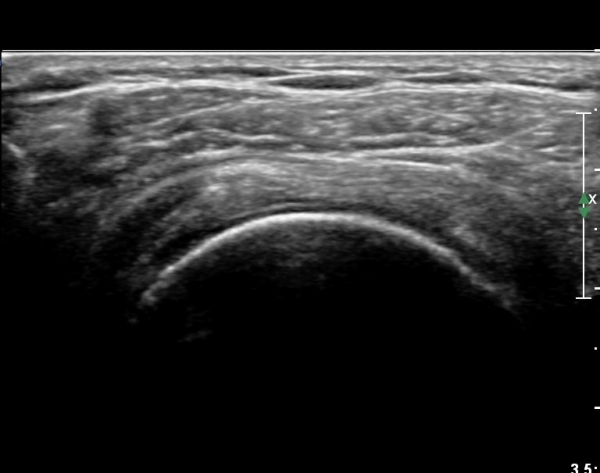

ȸÀü±Ù°³°£°Ý(rotator cuff interval) Ⱦ´Ü¸é°Ë»ç¿¡¼­ ÀÌµÎ¹Ú±Ù°Ç ¿ÜÃø¿¡ ±Ø»ó°ÇÀÌ °üÂûµÇÁö ¾Ê°í

´ë°áÀý Ç¥ÃþÀÇ »À°¡ ¿ïÅüºÒÅüÇÏ°Ô º¯ÇÏ¿´´Ù(±×¸² 1, 2)

ÀÌ´Â ½ÉÇÑ Ãæµ¹ÁõÈıºÀÇ °á°úÀ̰í ȸÀü±Ù°³ ÆÄ¿­À» °­·ÂÈ÷ ¾Ï½ÃÇÏ´Â ¼Ò°ßÀÌ´Ù.